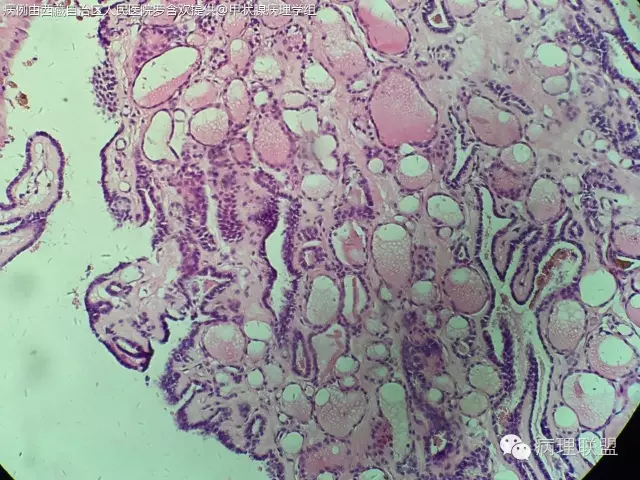

打脸病例分享,52/F,19年前因右侧甲状腺腺瘤行局部切除,因甲状旁腺功能亢进行甲状旁腺摘除,术中送检部分右侧甲状腺组织,冰冻切片未见异常,常规石蜡切片见乳头状结构,乳头间质见沙粒体,镜下图片如下:

自己在镜下看了半天核是有点挤,我们苏木素染色有点深,没看出有啥核沟和包涵体。因为出现沙粒体,上级医生不放心,加做免疫组化:

微小乳头状癌。这种结构有时看不到典型的核的特点。@毕超

@阳宇 我之前还觉得没有核特征不能下癌,这例的不典型是否和冰冻有关?我们染色有点深

嗯嗯。个人觉得跟冰冻有些关系,还待其他老师高见

第一例乳头内有滤泡,第二例是真正纤维轴心,两例乳头不一样

PTC.核已经出现拥挤参差不齐,卵圆形有异性,加上沙立体的出现标准已够。实际上出现沙立体意味着PTC.但是要区分滤泡腔内深染浓缩的胶质。还有PTC强调在正常滤泡背景中的突然性,两者不能有移形。